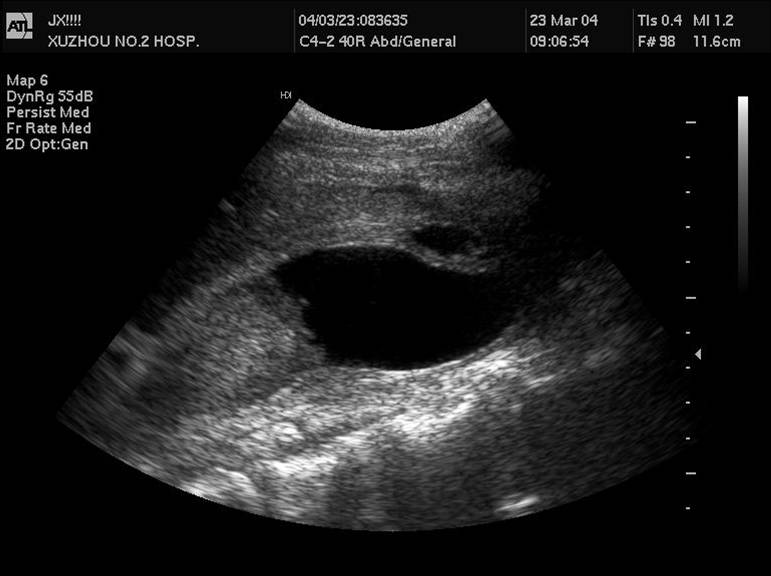

3 先天性胆管囊状扩张症